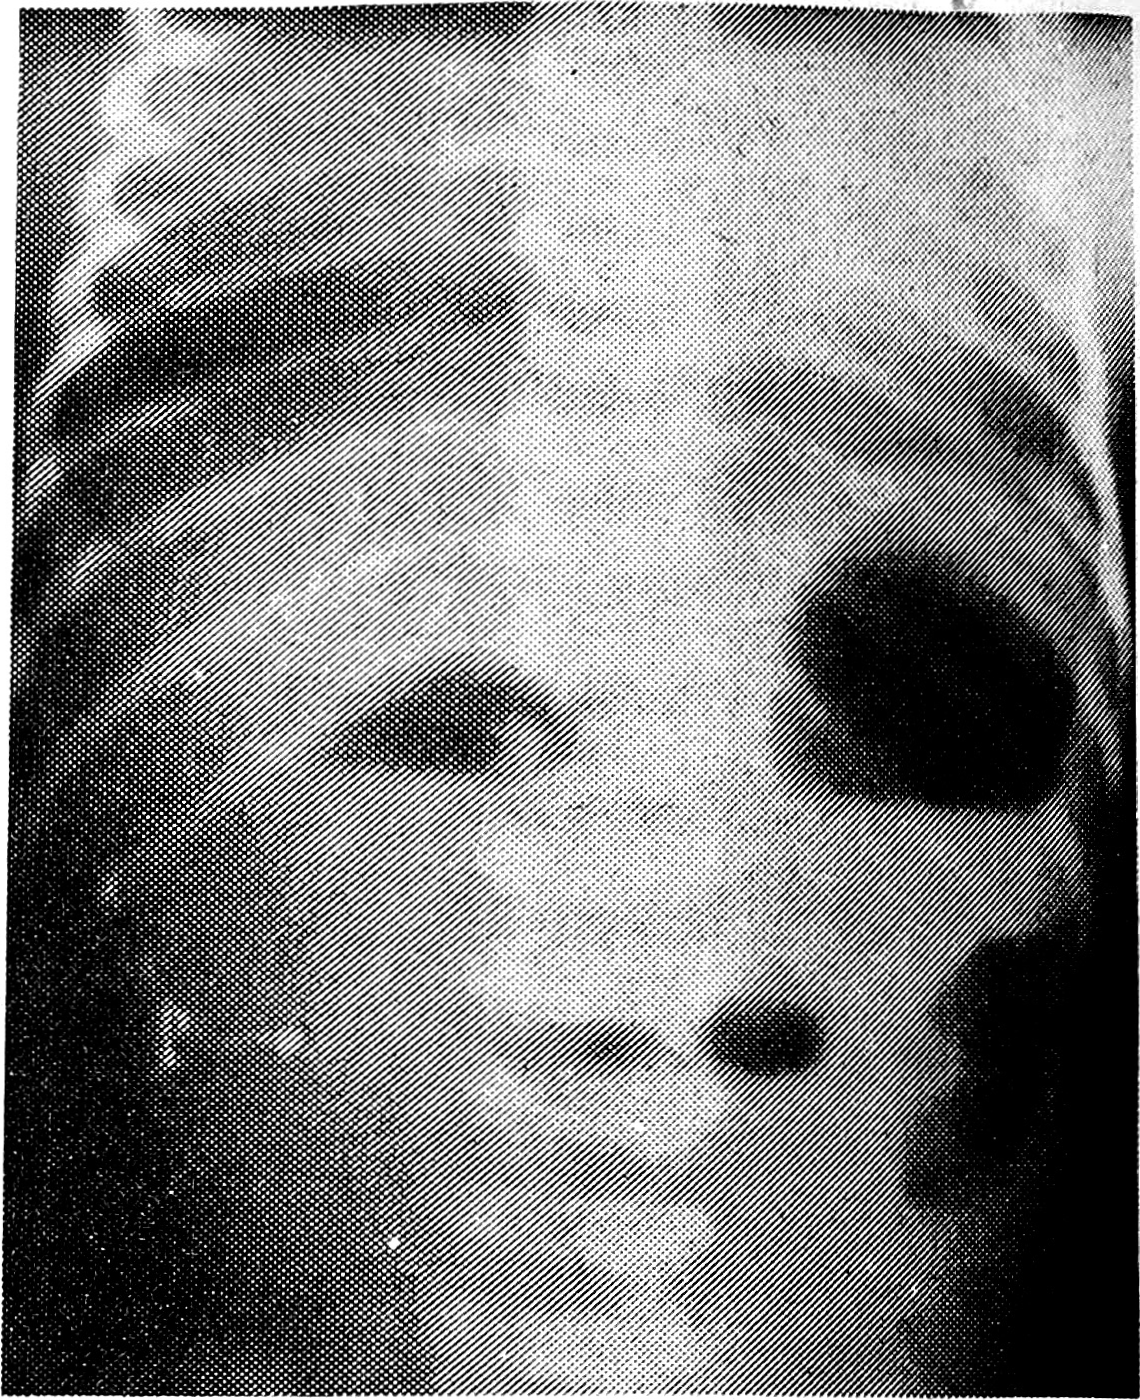

В наших исследованиях случаи пилоростеноза характеризовались такими клиническими показателями, как рвота фонтаном с 20— 25-го дня жизни ребенка (у всех 23 детей), видимая перистальтика желудка (у 17), нарастающий дефицит массы тела (у 19), запоры и редкое мочеиспускание (у 23). Рентгенологически отмечались удлинение пилорического канала в виде усиков, антрального клюва, пунктирной линии (у 13), задержка эвакуации из желудка от 12 до 24 ч (у 22), скудное количество газа в кишечнике (у 13). Приводим рентгенограмму желудочно-кишечного тракта ребенка с врожденным пилоростепозом желудка (рис. 2).

Рис. 2. На обзорной рентгенограмме брюшной полости ребенка 2 мес после приема контрастной взвеси определяется скудное количество газов в петлях кишечника. Желудок увеличен в объеме, видимая перистальтика, отсутствие эвакуации бариевой взвеси из желудка. Пилоростеноз.